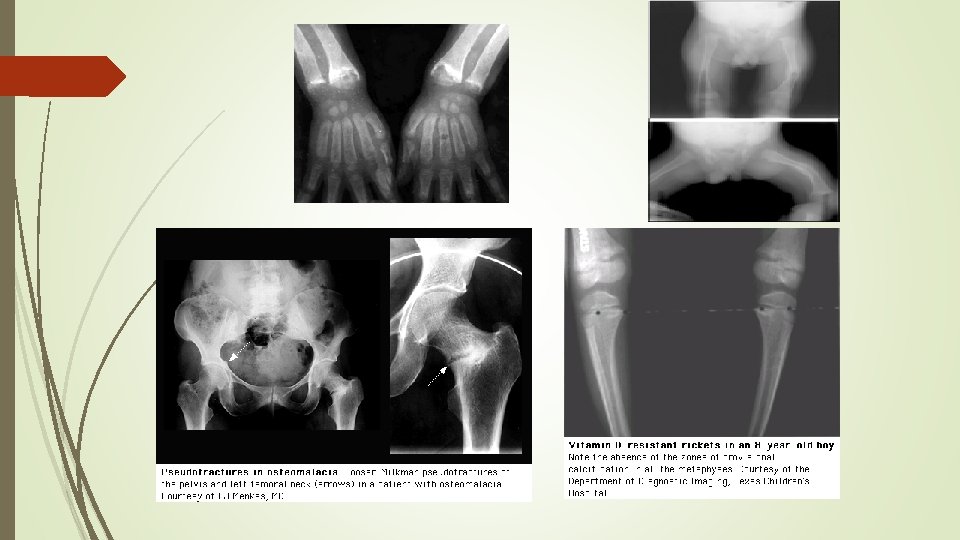

Radiographic findings Ø cupping Ø widening of the epiphyseal plate Ø fraying of the metaphysis

radiographs of a child with hypophosphatemic rickets, Metaphyseal widening in wrists And knees bone rarefaction

Anteroposterior radiograph of the knee in a 5 -year-old girl with XLHR partial fraying irregularity of the distal femoral proximal tibial growth plates (upper and lower arrows, respectively)

Looser zone (pseudofracture)

Anteroposterior pelvic show enthesopathy (arrows) in a 48 -yearold woman with Xlinked hypophosphatemic osteomalacia. Note sacroiliac joint sclerosis (arrowheads )